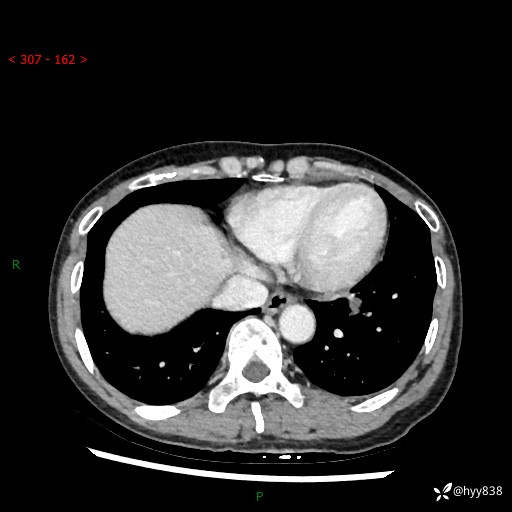

【检查】:胸部CT平扫+增强

各期CT值:40hu 57hu 49hu